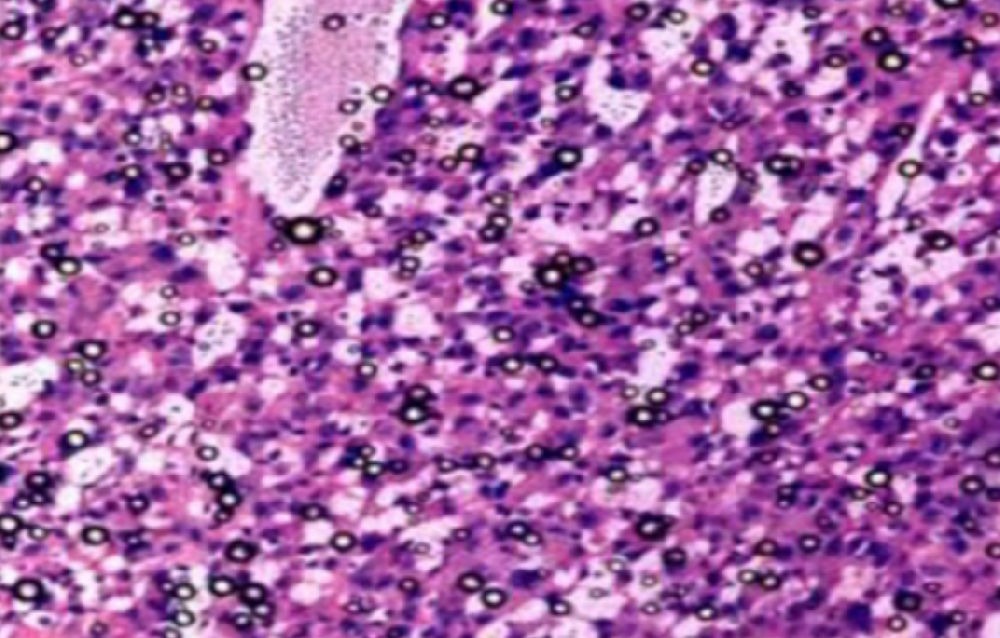

1、电镜成像:透射电子显微镜观察法(TEM)是从形态和大小上对外泌体进行鉴定通过负染的方法,在高倍放大下直接观察单个外泌体的形态结构和大小。但电镜会有背景的干扰,且无法区分外泌体和与其形态相近的粒子。